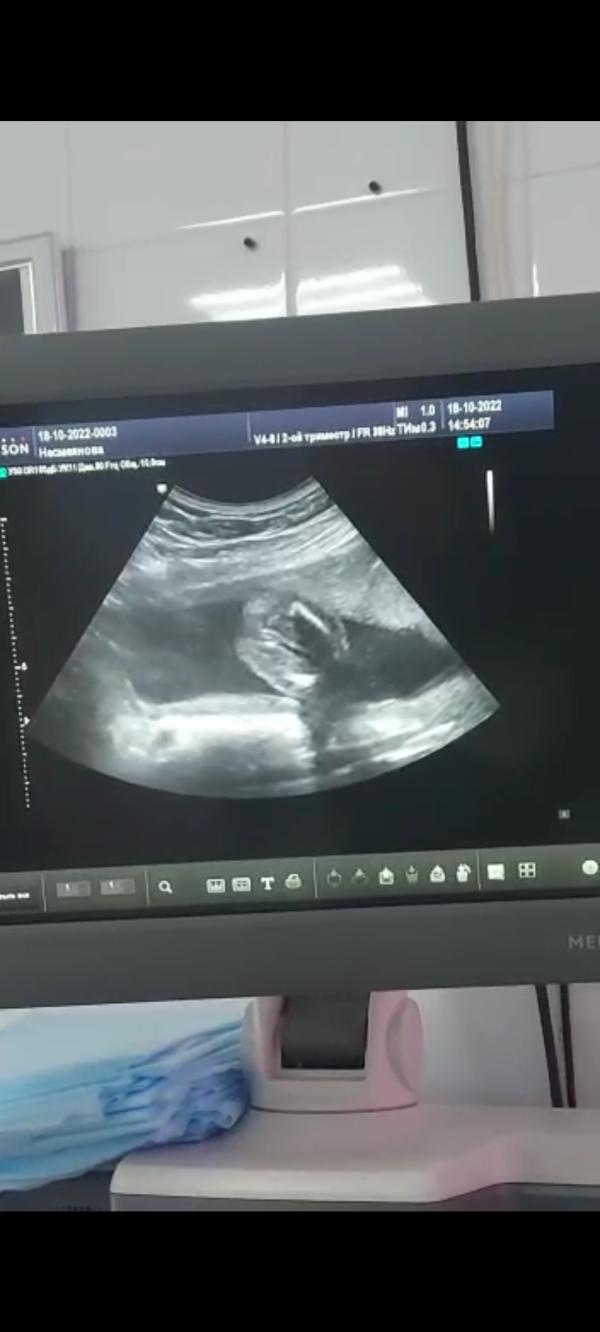

Платное УЗИ показало девочку на 17-18 неделе: как думаете, достоверно? Ваши мнения!

Всем привет ,сказали на платном узи девочка 17-18 недель как думаете похоже?)

Девочка подтвердили)